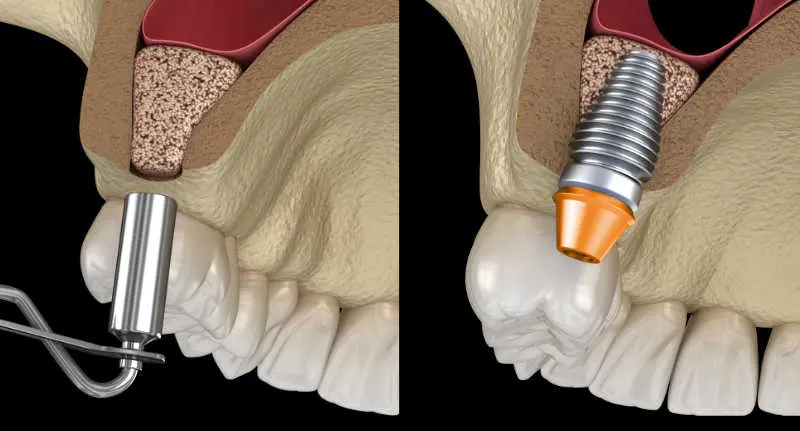

Our implants are made of grade 5 Titanium, making them 100% biocompatible with the human body. We work with the best implant brands worldwide STRAUMANN® and NEODENT®. Implants are surgically placed in the maxillary bone under the gum to replace both functionally and aesthetically one or more missing teeth.

- Perhaps the most important thing to note is that implants fulfill the function of the root when a tooth has been lost. In the absence of a root, the bone loses strength and thickness contributing to its deterioration and the movement of the adjacent teeth.